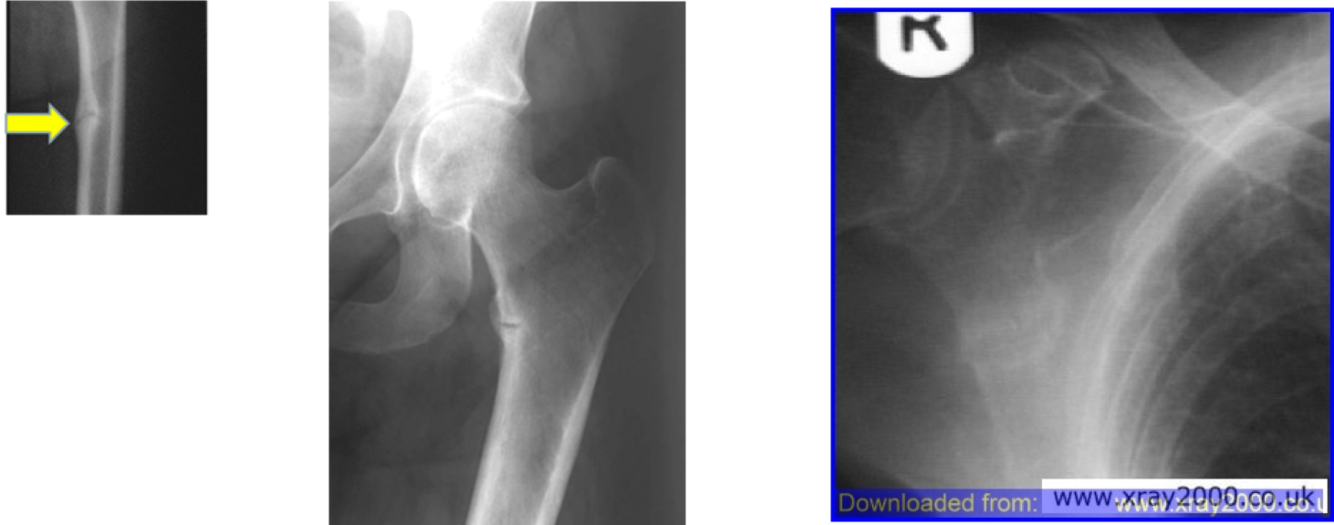

Rickets and Osteomalacia

what is Rickets and Osteomalacia?

Severe nutritional vitamin D or Calcium deficiency causes insufficient mineralisation and thus Rickets in a growing child and Osteomalacia in the adult when the epiphyseal lines are closed

Vitamin D stimulates the absorption of calcium and phosphate from the gut and calcium and phosphate then become available for bone mineralisation

Muscle function is also impaired in low vitamin D states

how does Rickets present in a child?

stunted growth

Abnormal bone growth

Boing of leg bones

Large abdomen

Odd shaped ribs

Rare in UK due to nutritional problems

Simply treated with calcium and vitamin D supplements

Osteomalacia - who is it common in, what is the symptoms and what is the treatment?

Common in elderly

Symptoms: bone pain, muscle weakness, increased falls risk

May see micro fractures on x-ray – lucre zones

Calcium and vitamin D supplements for treatment